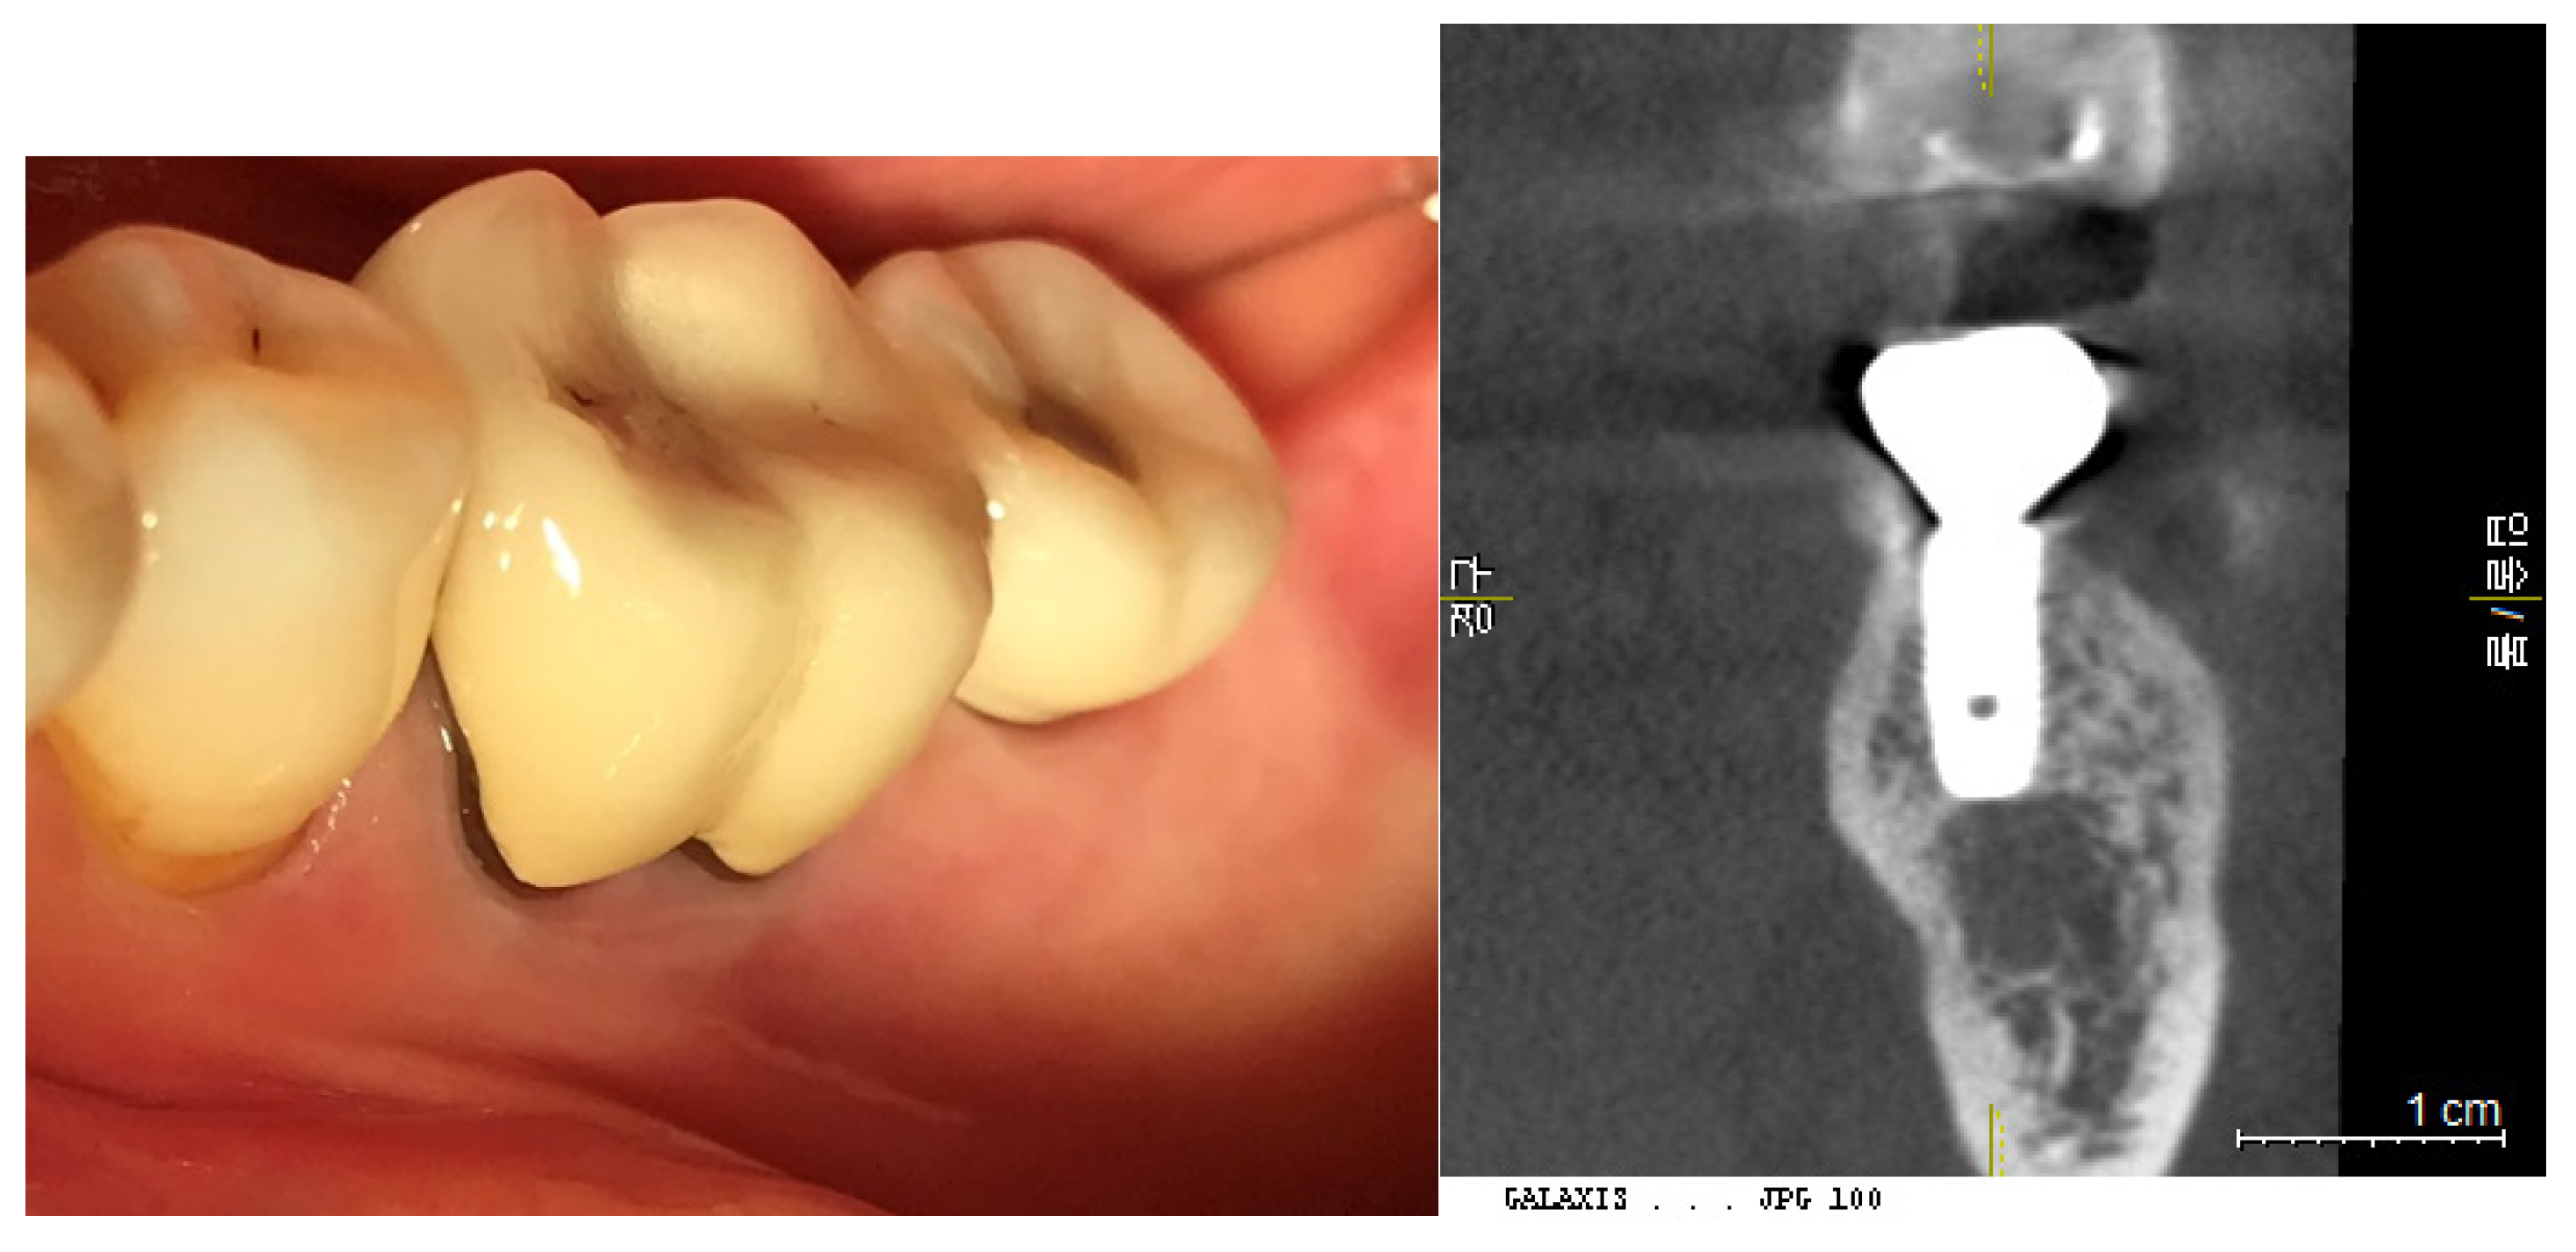

Figure 11. Calibration of CBCT Images. This figure demonstrates the calibration process where images are coordinated along the long axis of the fixtures. This alignment is crucial for accurate measurement and analysis, ensuring that the fixture dimensions are accurately reflected in the CBCT images.

2. Measurement of Placement Depth (PD) from CBCT - 3DSTA

Placement depth was assessed using CBCT in the 3DSTA context, focusing on both the central and peripheral areas in mesiodistal and buccolingual aspects:

a) Central Placement Depth (cPD): - The depth at the central area was measured as the perpendicular distance from the top point of the crestal bone to the platform of the implant fixture at its most outer point (e.g., at the 5 mm point of a 5 mm diameter fixture).

b) Peripheral Placement Depth (pPD) - Mesiodistal and Buccolingual Aspects: - In the mesiodistal aspect, the depth was measured as the perpendicular distance from the top point of the crestal bone to the platform of the implant fixture at the most outer point of the crown. - In the buccolingual aspect, the depth was measured from the most coronal top point of the crestal bone to the platform of the implant fixture.